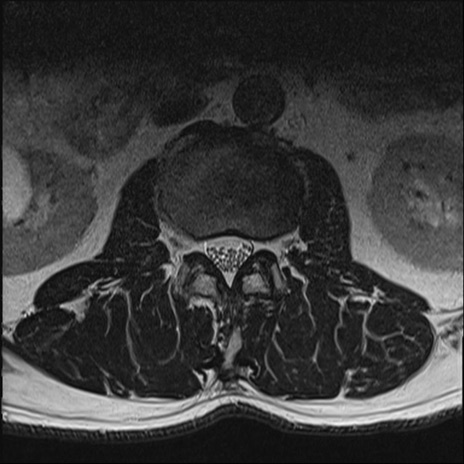

【整形】TIPS症例2 腰椎MRI T2WI(横断像)

【症例】70歳代男性

【主訴】左下肢痛

【現病歴】2週間前くらいから腰痛、左下肢痛あり。左臀部から大腿、下腿外側のしびれが常時ある。歩行とともに同部位の痛みあり。

【身体所見】Lasegue70-/60+、Bragard-/±、PTR ±/±、ATR -/-、IP 5/5、TA 5/4、TS 5/5、EHL 右第1足趾なし/3、FHL 5/5、hypersthesia(-)、足背動脈触知良好

異常所見と診断は?